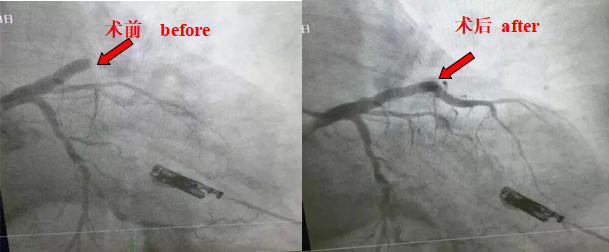

Case 1: 21-year-old, male, sudden chest pain for 4 hours, diagnosis: acute myocardial infarction.

Besides normal medication, percutaneous coronary intervention (including coronary angiography and coronary stent implantation), radiofrequency ablation (paroxysmal supraventricular tachycardia, atrial flutter, atrial fibrillation, ventricular premature, ventricular tachycardia), IABP (intra aortic balloon counterpulsation) implantation, structural heart disease intervention, left atrial appendage occlusion, permanent pacemaker (VVI, DDD, CRT, ICD) implantation and other advanced diagnosis and treatment are adopted. Cardiac color Doppler ultrasound examination can completed bedside. TCM, western medicine and the combination of TCM and western medicine treatment are provided for patients with cardiovascular diseases. At present, specialized outpatient service is provided: outpatient service for chest pain, atrial fibrillation, and hypertension center.